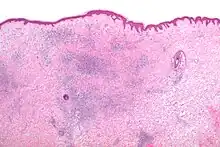

Microscopic appearance

Skin biopsies are not indicated for bites or stings, since the histomorphologic appearance is non-specific. Bites and stings as well as other conditions (e.g. drug reactions, urticarial reactions, and early bullous pemphigoid) can cause microscopic changes such as a wedge-shaped superficial dermal perivascular infiltrate consisting of abundant lymphocytes and scattered eosinophils, as shown in the adjacent figure:[12]